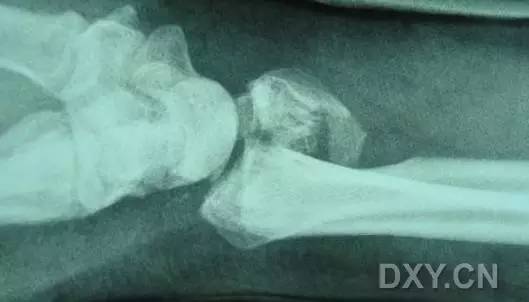

2. Colles 骨折

桡骨远端骨折,伴有桡骨远端向背侧的移位,可以有或没有尺骨干的骨折。具有这几个特征:背侧粉碎、向背侧成角、向背侧移位且挠骨短缩的关节外骨折。

典型 colles 骨折,枪刺样、餐叉样畸形